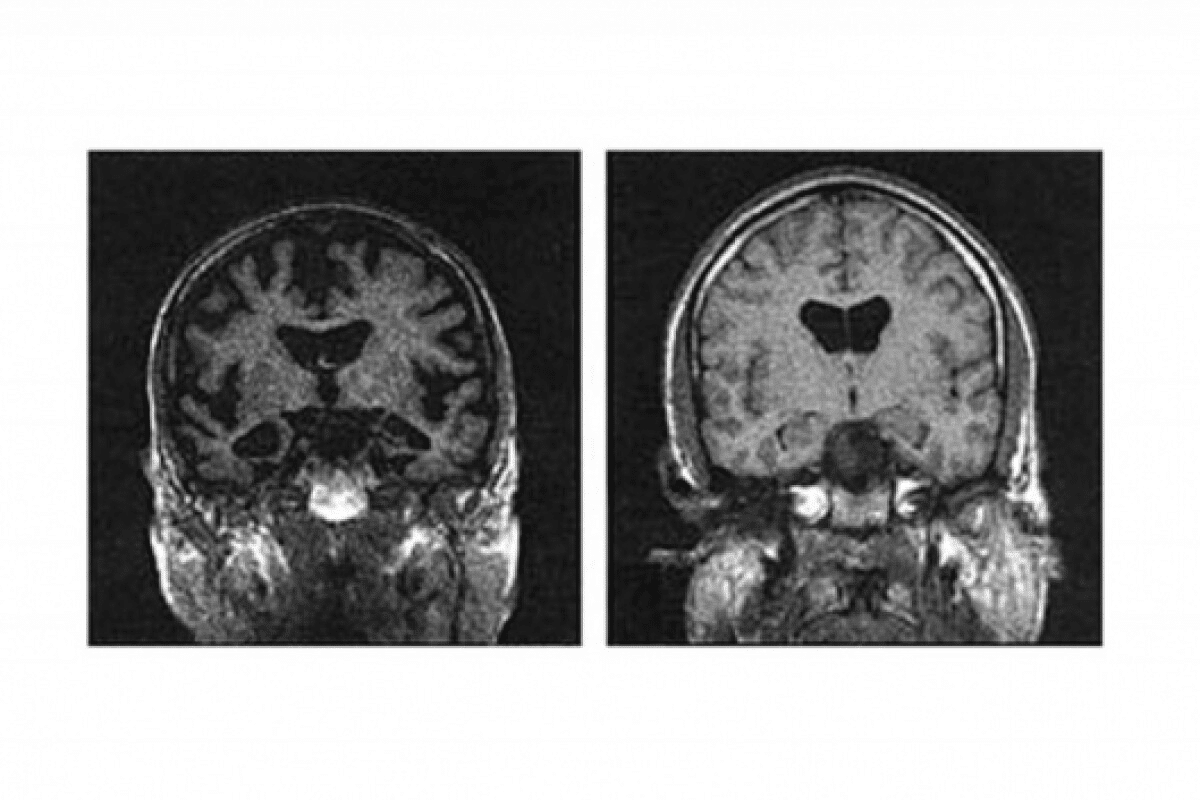

Neuroanatomical Progression of Alzheimer’s Disease

Alzheimer’s disease changes the brain in a specific way. It causes amyloid plaques and tau tangles. These changes lead to brain shrinkage and affect certain areas more.

Deterioration of Hippocampal and Entorhinal Cortex

The hippocampus and entorhinal cortex are hit early by Alzheimer’s. The hippocampus is key for memory. Its damage leads to episodic memory loss, an early sign of the disease.

The entorhinal cortex connects the hippocampus to the neocortex. Its damage messes up information flow. This worsens cognitive decline.

Temporal, Parietal, and Frontal Lobe Changes

Other brain areas like the temporal, parietal, and frontal lobes get affected too. The temporal lobe, important for hearing and memory, shrinks a lot.

The parietal lobe, key for sensing and spatial awareness, also degenerates. This causes problems with spatial skills.

The frontal lobe, which handles decision-making and movement, gets hit later. This leads to changes in behavior and motor skills.

Progressive Brain Atrophy and Regional Specificity

Alzheimer’s causes the brain to shrink over time. Some areas are more prone to damage than others. This is a key feature of the disease.